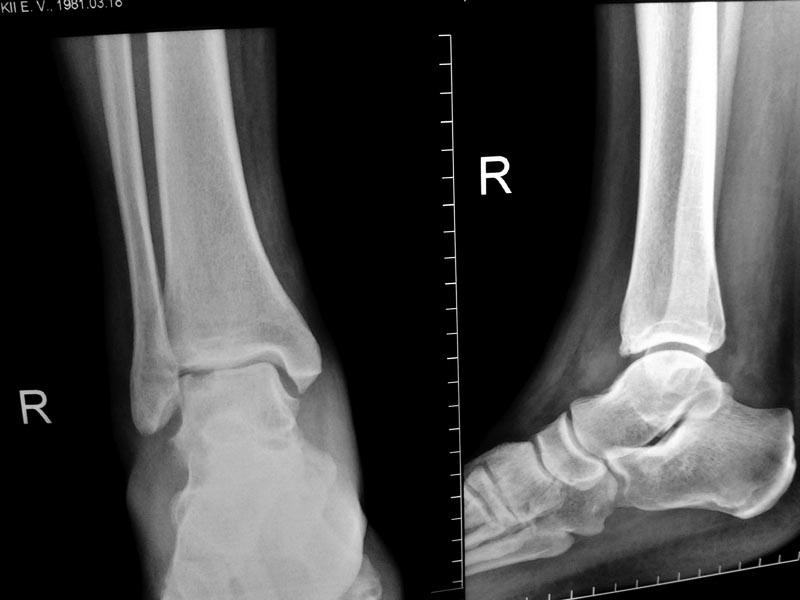

У 40-летнего мужчины около 3 месяцев появляются боли и отек в правом голеностопном суставе. Травмы, перегрузки, спорт и вредные привычки отрицает.

На Рграммах 2 месячной давности патология стопы не видна\качество снимков низкое\ На свежих снимках виден глубокий некроз блока тарана.Отек, хромота и боли стихают после терапии НПВП. Выбираем тактику- открытая артротомия латеральным доступом с остеотомией лодыжки и костная аутопластика после кюретажа. Вторым вариантом видится артроскопическая ревизия сустава, остеоперфорация дрелью под визуальным контролем и 8 недель разгрузки сустава в АВФ.Патология досточно редкая и буду признателен за совет коллег, кто уже работал с такими пациентами.

Дефект глубокий, обширный, в молодом возрасте лучше оперировать. Иногда в выборе доступа помогает КТ в положении максимального подошвенного сгибания стопы: если дефект таранной кости при этом выходит из-под большеберцовой, лучше идти простым и менее травматичным передним доступом. На монтаже из представленной Вами рентгенограммы стопа согнута на 30°, дефект практически "вышел". Поскольку он расположен не по центру, то с большой степенью вероятности обнажится при гораздо меньшем угле.